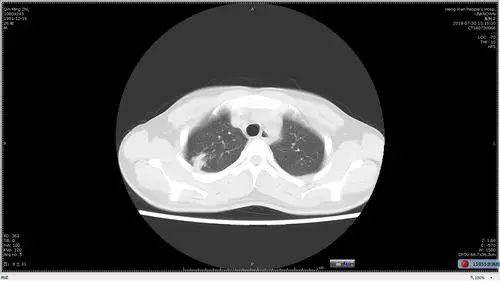

多发小结节状卫星灶的肺结核